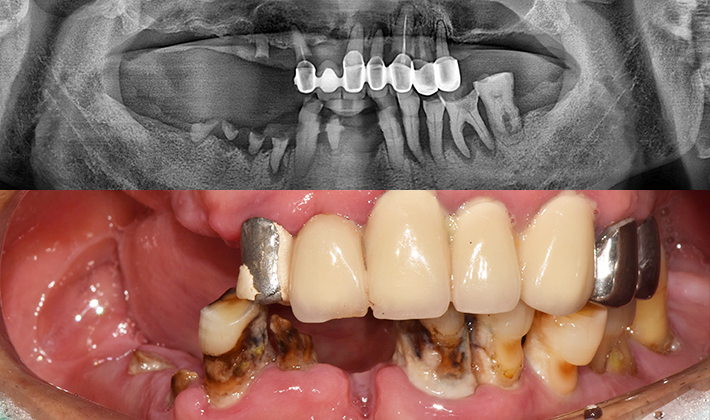

치과가 무서워 10년 동안 미뤄온 임플란트 수술 그 결과는?

2026.01.21